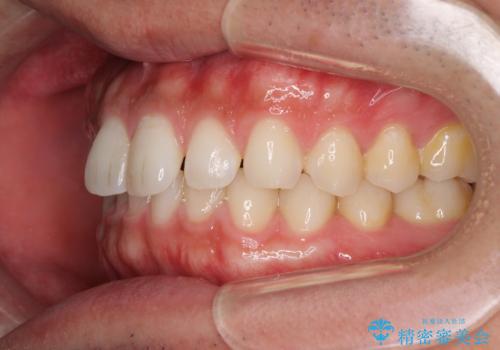

細かい隙間にものがはさまる インビザラインによる矯正治療

- 上下の前歯の隙間を気にして来院された患者様です。

インビザラインを用い、上下歯列のスペースを閉じていくこととしました。

銀行にお勤めのため、突然の転勤により通院が大変な状況となりましたが、インビザラインであれば2-3ヶ月に1度を目安に来院いただき、無事に治療を終えることができました。